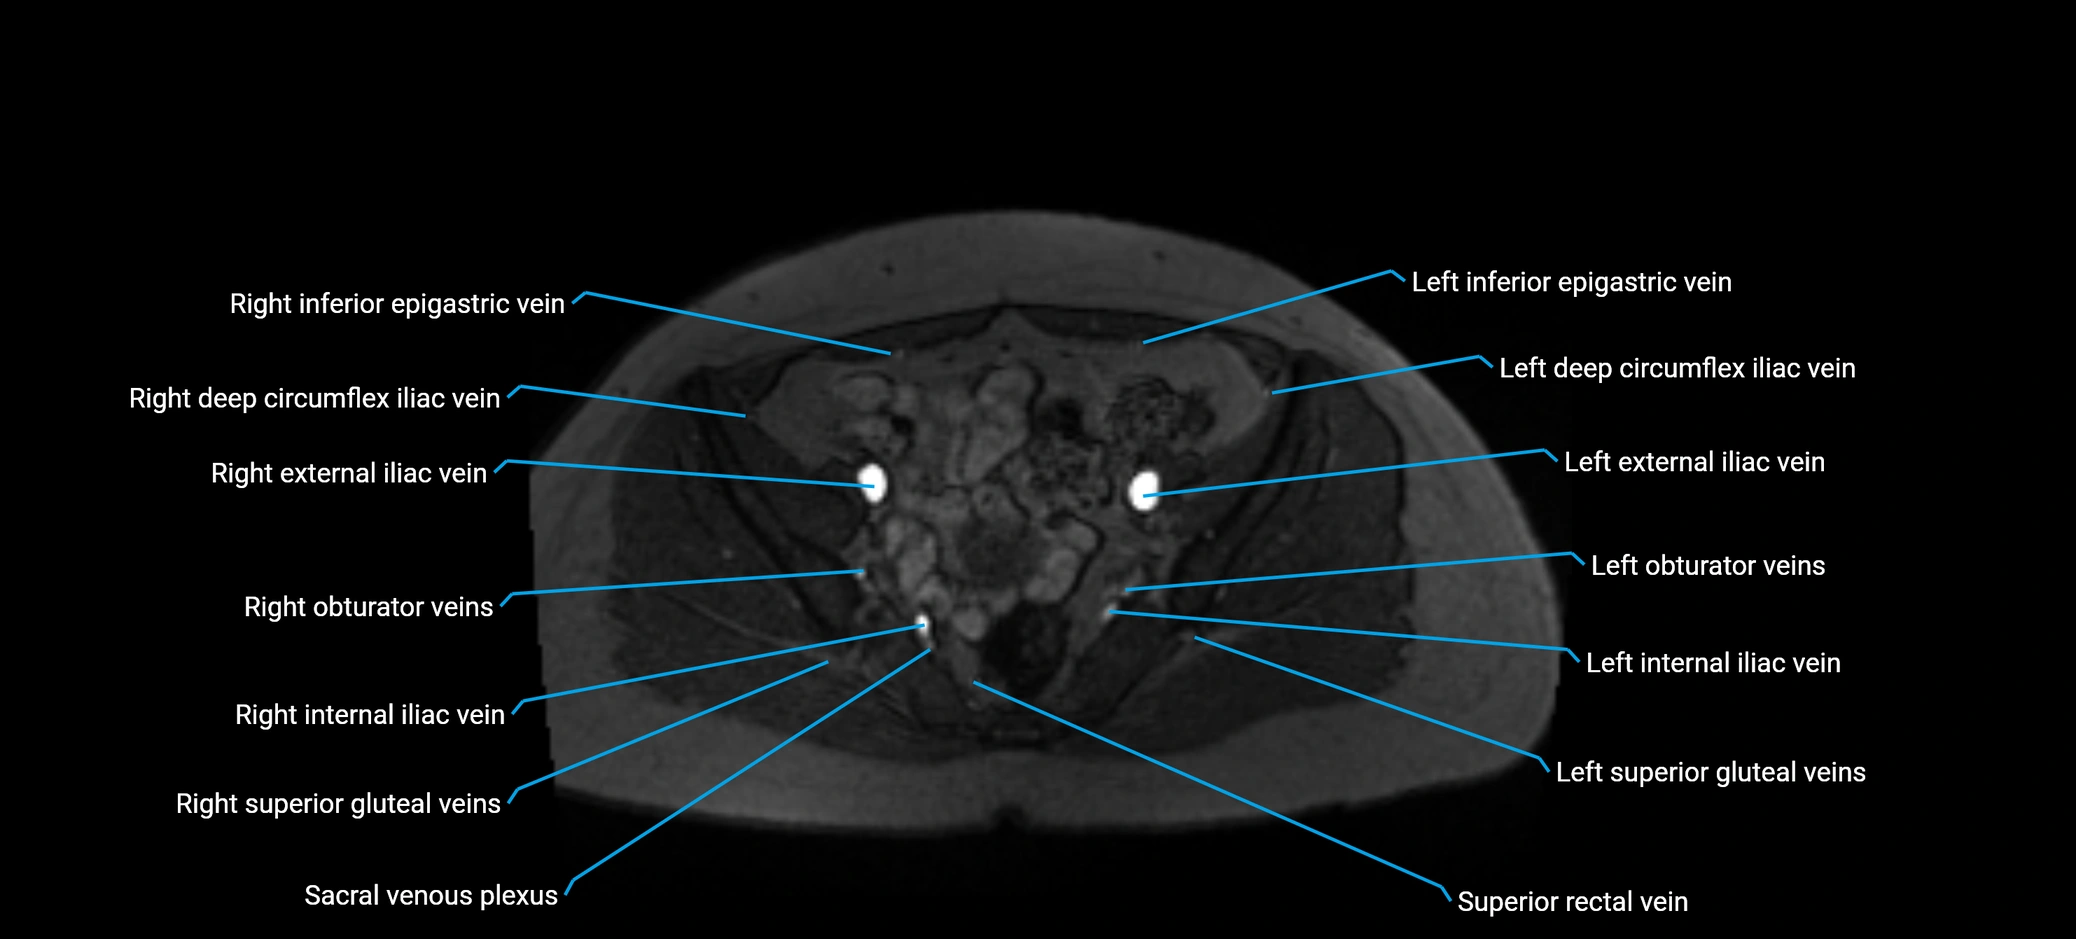

MRI image

image